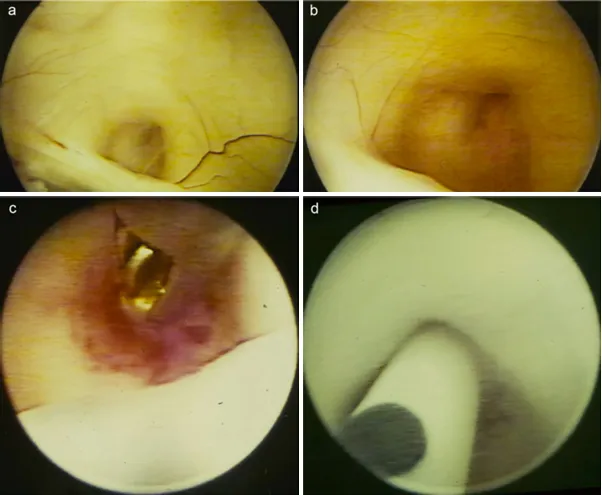

施罗德教授迅速决定为该男孩实施内镜下第三脑室造瘘术、肿瘤活检术以及经导水管支架置入术(图2)。

图2:术中内镜视角,位于后连合上方被闭塞的导水管(a、b)。在内镜活检后(c),通过导水管将导水管支架置入第四脑室(d)。